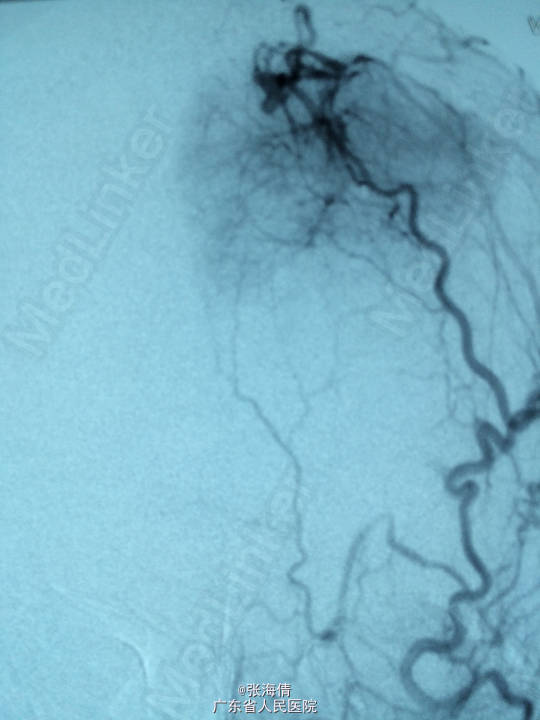

诊断:脑膜瘤 处理:先予DSA以明确肿瘤供血情况,术中脑膜瘤供血丰富,用PVA颗粒超选到供血动脉将其闭塞。后再择期在气管全麻下行脑膜瘤切除术。

术后病理提示:脑膜瘤,WHO I级,瘤组织浸润脑组织。免疫组化:Ki一67(<1%)(+),CK(一),GFAP(一),Vimentin(+),EMA(+),P53(一),ER(一),PR(一)。 讨论:脑膜瘤首选方法为手术切除,手术切除脑膜瘤是最有效的治疗手段,但是由于其供血经常较为丰富,故可先行介入栓塞供血动脉后再行切除,这样可以降低手术风险和手术难度,改善患者手术预后。